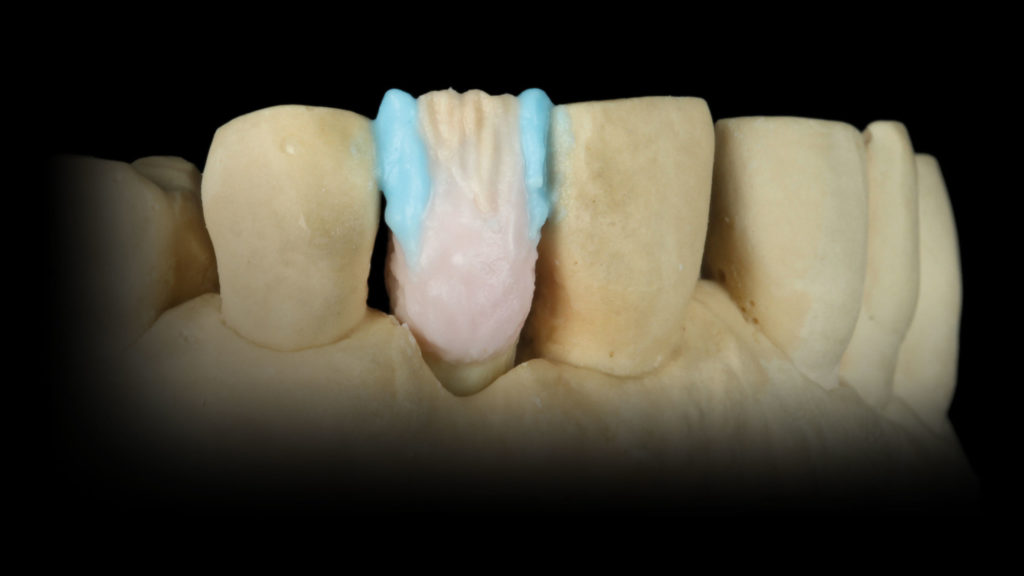

Nachdem die Farbanalyse abgeschlossen war, wählten wir die für die keramische Verblendung erforderlichen Massen gemäß der Referenztabelle des Ceramco 3-Systems aus. So wurde gewährleistet, dass wir das, was wir analysiert haben und nachahmen wollten, auch mit den entsprechenden Massen nachahmen konnten (Abb. 10). Den Anfang machte das Opakern des Metallgerüsts. Dafür kam der Ceramco 3-Pastenopaker zum Einsatz, auf den noch zusätzlich der systemimmanente Pulveropaker gestreut wurde. Dies sorgte für eine rauere Oberfläche, an der sich das Licht diffus brechen konnte. Nach dem Brand stellte sich das Ergebnis wie in Abbildung 11 zu sehen dar. Der Behandler hatte als Grundzahnfarbe die A3,5 und für den freiliegenden Wurzelbereich B4 ausgewählt. Dementsprechend wurden die Massen gewählt (Abb. 12 und 13). Darüber hinaus verwendeten wir, wie aus den Fotografien, die mit Kreuzpolfilter angefertigt worden waren, ersichtlich (vgl. Abb. 8a und b), im inzisalen Drittel eine Dentin-Masse mit geringerem Helligkeitswert (Abb. 14 und 15).

Mit einer dünnen Schicht der 1:1:1-Mischung aus den Mamelon-Massen Gelb-Orange und Rot-Orange sowie der Modifier-Masse Pink Dentin wurde eine höhere Farbsättigung erreicht (Abb. 16). Um die Transluzenz zu den Flanken hin zu verstärken, wurden die Schmelzmassen Natural Enamel Light und Clear im Verhältnis 1:1 angemischt und mesial und distal aufgetragen (Abb. 17). Der Raum zwischen diesen Schmelzleisten wurde labial, aber auch palatinal mit einer 1:1:1-Mischung aus Light, Super Clear Glaze und Violet Glaze gefüllt (Abb. 18 und 19). Ein Streifen des Dentin Modifiers Violett sorgt im mittleren Drittel für einen Lichtabsorptionseffekt (Abb. 20a und b). Nach dem ersten Brand kann man gut erkennen, ob uns der Grundkörper gelungen ist (Abb. 21) oder ob wir den inneren Aufbau intensivieren, reduzieren oder andere Änderungen vornehmen müssen.